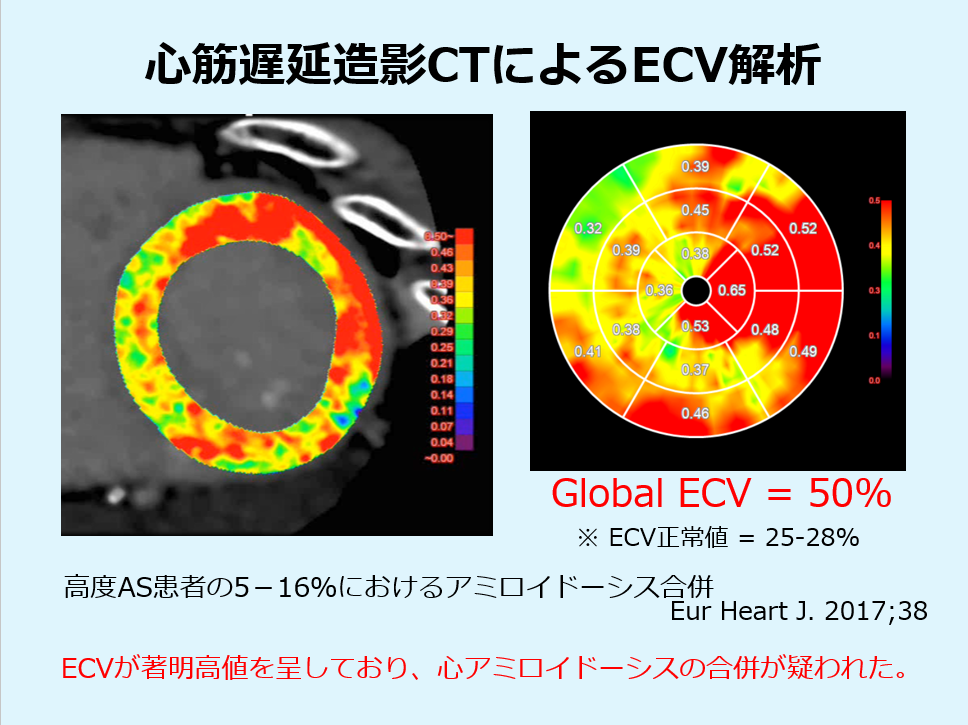

心筋遅延造影CTを撮影することで、MRIでの心筋ダメージの指標として確立している細胞外容積分画(ECV)をCTから算出することができます。

ECV50%と極端な異常値を呈しており、心アミロイドーシスを疑う所見でした。

視覚的な遅延造影は淡いコントラストであり、評価が難しい。ECV解析にて明らかな異常が顕在化

ワークステーションはZIOを使用